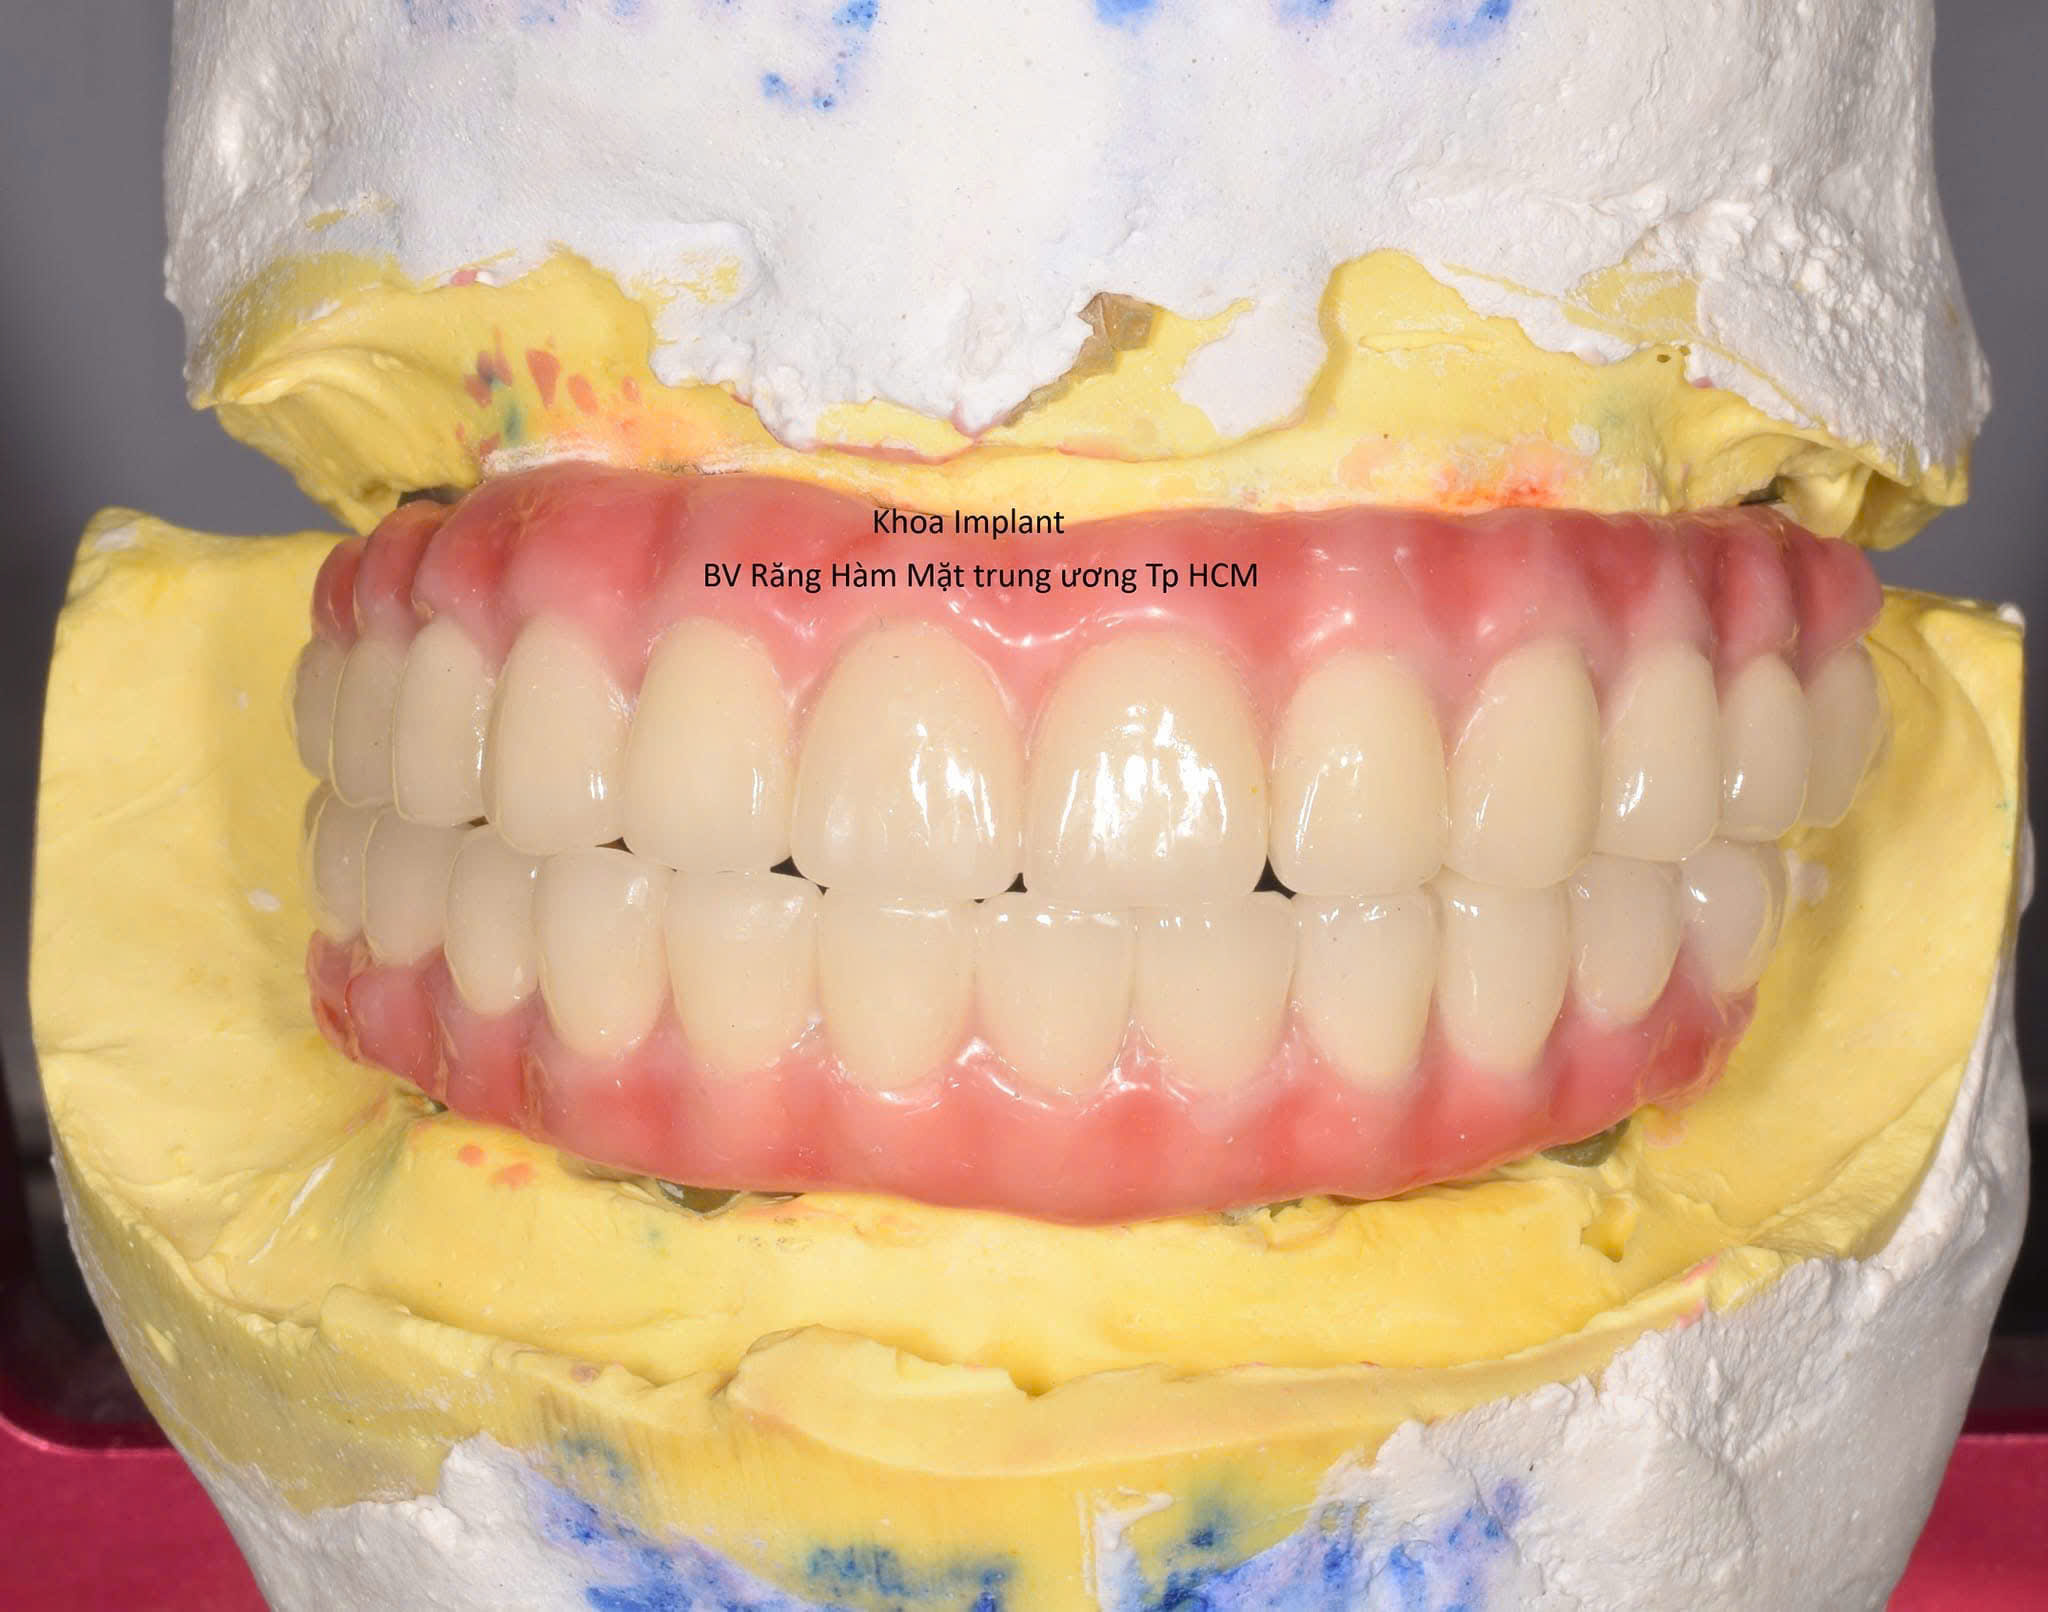

Phân khoa Cấy ghép răng, trực thuộc khoa Phẫu Thuật Hàm Mặt, được Viện thành lập vào tháng 5/1999. Khoa Cấy ghép răng chính thức được Bộ Y t ế công nhận vào năm 2004. Nguyên Viện trưởng, PGS. TS. Lâm Ngọc Ấn cùng với các Bác sĩ nước ngoài đã thực hiện ca implant đầu tiên tại Việt Nam ngày 10/1/1994, đến nay, sau 26 năm vẫn còn sử dụng tốt. Hiện nay khoa thực hiện được hầu hết các kỹ thuật trong implant như Nâng xoang, các kỹ thuật tăng thể tích xương và mô mềm, đặt implant xương gò má, phẫu thuật dời dây thần kinh răng dưới, phục hình dưới sự hỗ trợ của kỹ thuật số… nhờ đó khoa có thể giải quyết được hầu hết các trường hợp lâm sàng từ đơn giản đến phức tạp.

Phục hình trên bệnh nhân cắt đoạn xương hàm và ghép xương tự thân

1. Công nghệ – Số hóa

Phát triển hệ thống implant số hoá toàn diện.